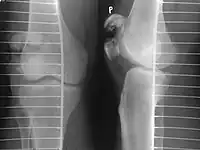

Patella fracture

| A fracture of the patella seen on a lateral view | |

A patella fracture is a break of the kneecap.[1] Symptoms include pain, swelling, and bruising to the front of the knee.[1] A person may also be unable to walk.[1] Complications may include injury to the tibia, femur, or knee ligaments.[2]